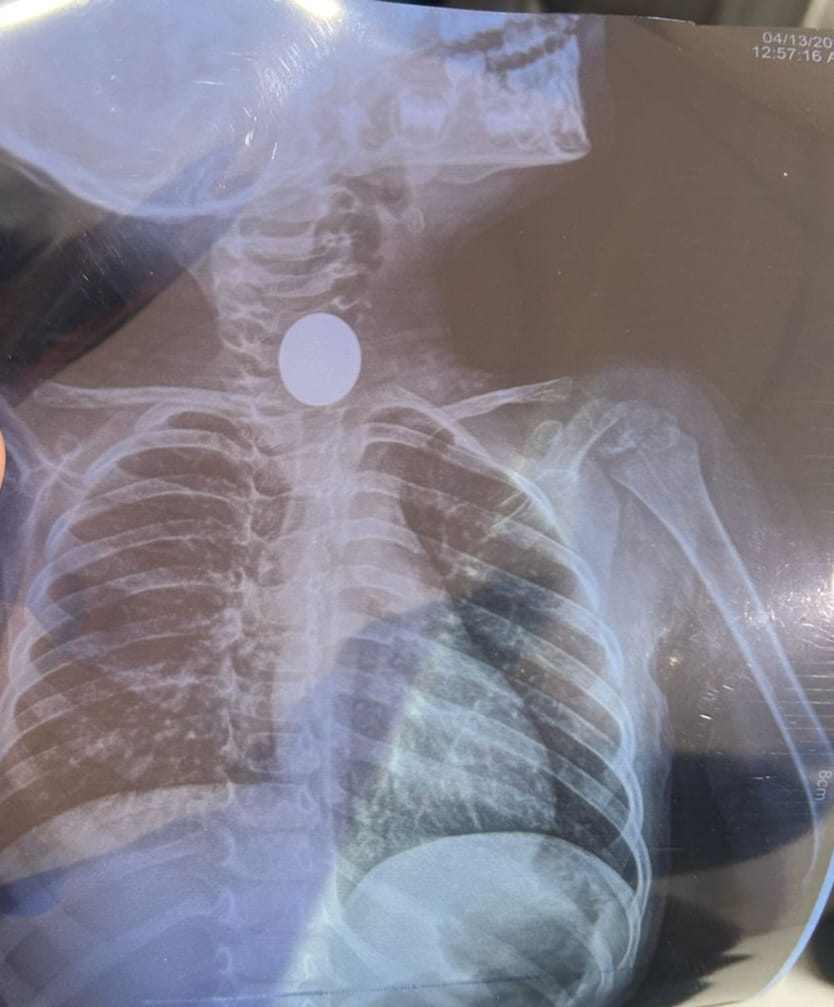

التعامل مع الحالة الأولى بإجراء منظارمعدة طوارئ للطفل واستخراج عملة معدنية علقت أسفل صمام المرئ العلوي

وأوضح الدكتورهاني مصطفى جميعة وكيل وزارة الصحة بالشرقية بأنه تم التعامل مع الحالة الأولى بإجراء منظارمعدة طوارئ للطفل واستخراج عملة معدنية علقت أسفل صمام المرئ العلوي، حيث ابتلعها منذ ثماني عشرة ساعة وأدت إلى انسداد في مجرى الطعام والتهابات بجدار المرئ بسبب ضغط العملة على جدار المرئ، وإنقاذ الطفل قبل حدوث ثقب في جدار المرئ.